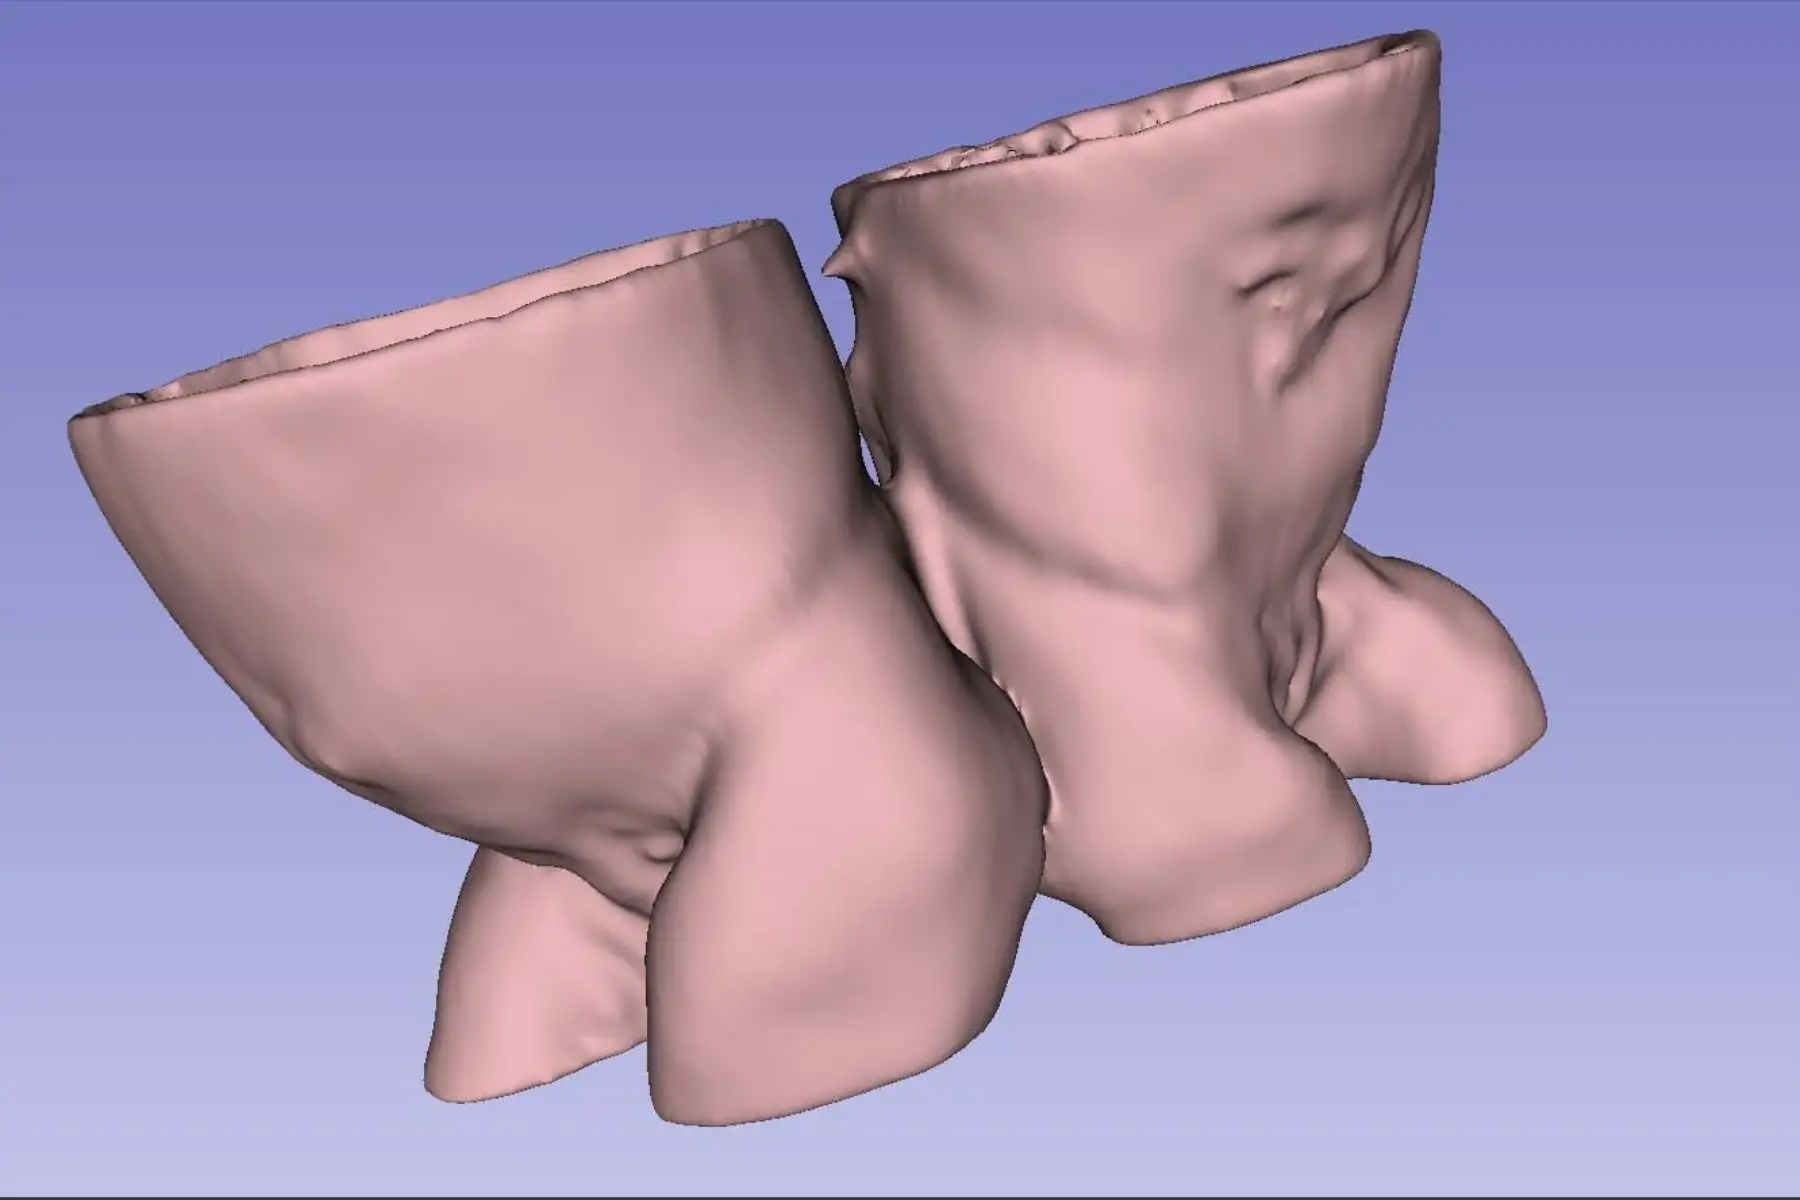

27/01/2026 Un equipo multidisciplinario del Instituto Nacional de Salud del Niño San Borja empleó modelos 3D y realidad virtual para planificar la compleja separación de las gemelas siamesas Ailani y Alif Palacios Picón, unidas por la columna vertebral. La tecnología permitió una visualización precisa de su anatomía antes de la cirugía realizada el 18 de diciembre, que culminó con resultados favorables en la evolución de ambas pacientes. Foto: ANDINA/Composición con fotos de Difusión

27/01/2026 La planificación quirúrgica incluyó simulaciones virtuales que permitieron al equipo médico analizar con anticipación las estructuras compartidas, reduciendo riesgos y optimizando cada etapa del procedimiento antes del ingreso a sala de operaciones. Foto: ANDINA/Composición con fotos de Difusión

27/01/2026 Los modelos anatómicos impresos en 3D fueron elaborados a partir de estudios de resonancia magnética, lo que facilitó una comprensión detallada del canal raquídeo y las estructuras nerviosas comprometidas en ambas pacientes. Foto: ANDINA/Composición con fotos de Difusión